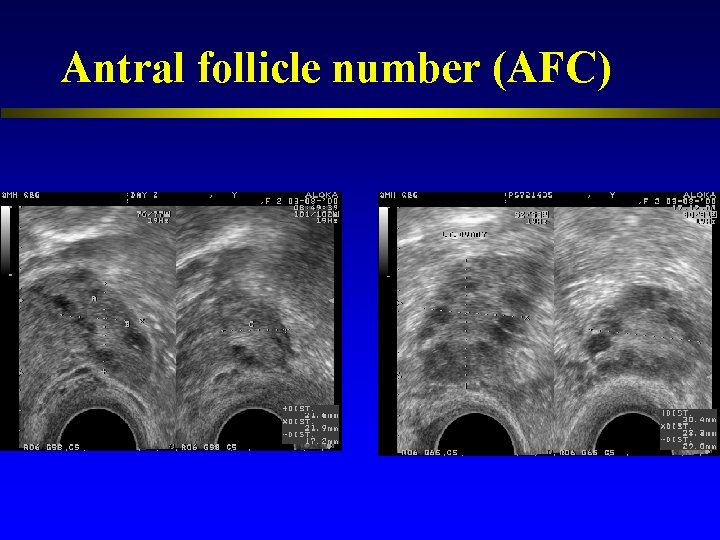

Antral follicle number (AFC)